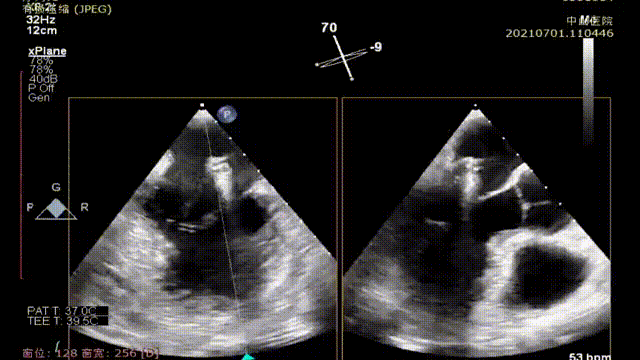

术中,王春生教授、魏来教授团队在超声引导下,仅用一个多小时就将3根人工腱索准确地锚定在患者二尖瓣脱垂病变区域,顺利完成了E-ChordTM人工腱索的植入,修复了患者的二尖瓣腱索,使二尖瓣恢复了正常功能。

术中器械释放过程